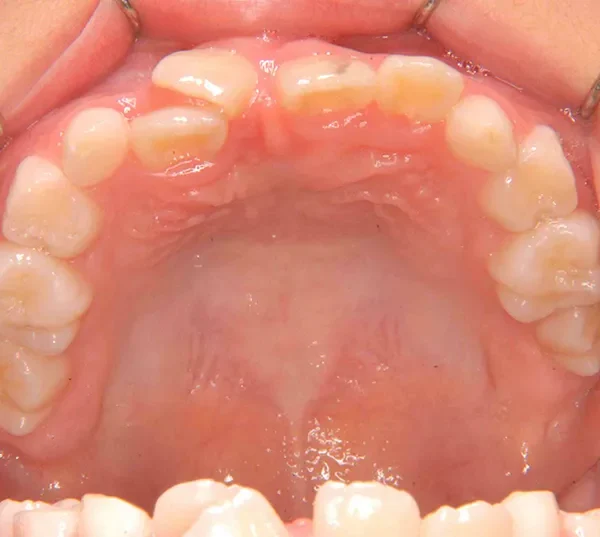

【子供の矯正(一期)】叢生・埋伏歯・受け口・永久歯が生える隙間がない・非抜歯症例・9歳女子【K.T様】

初診時年齢 小学校2年生 (女性) 主訴 受け口・がたがた

診断名 埋伏歯・反対咬合・叢生 装置名

拡大床

特徴 ゆがんで生えている

上の歯と下の歯で舌をはさむ癖がある

状態 永久歯が生える隙間がない(叢生)

受け口(下顎前突/反対咬合)

歯が埋まっている/歯がない(埋伏歯)

受け口で、ガタガタが有りました。

レントゲンを撮ってみると犬歯の萌出方向がずれていました。

先ずは萌出スペースを確保してから開窓術を行い、犬歯を正しい方向へ誘導しました。

マルチブラケット装置は使わずに、最低限の必要な装置を使って目立たないように治療しました。

初診